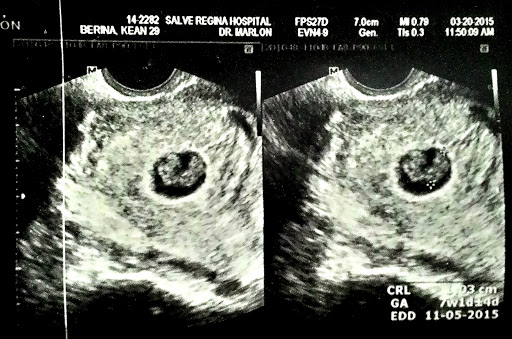

TVS. No fetal heartbeat was detected. My OB wanted us to get a second opinion so she referred us to the hospital she's affiliated to get a bigger picture of the sonogram. She reminded me to let her know the result as soon as I get it and that we will see each other at the hospital in a few.

We rushed, got some ultrasound and the sonologist found two babies. I got excited! Unfortunately, he can't detect a single heartbeat. I can sense the hope and disappointment in his face. He keep on trying, waiting for the heartbeat, but there was none. I wanted to cry. But I tried to keep my composure. It was the fastest but longest minutes of my life. Fast because I can't believe that I lost them that easy. And long because it took me some time to realize that I am no longer pursuing the pregnancy.

My OB came, gave her the result and I saw how sad she was, especially after seeing that I was supposed to have twins. But we are all positive and my safety is our concern at the moment. Since the babies died inside, I have to undergo D&C to avoid complications and infections.